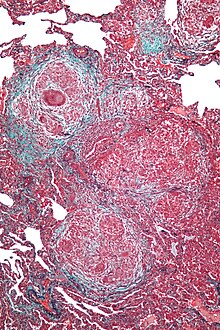

The acute form can be characterized by poorly formed noncaseating interstitial granulomas and mononuclear cell infiltration in a peribronchial distribution with prominent giant cells.[1] The subacute, or intermittent, form produces more well-formed noncaseating granulomas, bronchiolitis with or without organizing pneumonia, and interstitial fibrosis.[1] Much like the pathogenesis of idiopathic pulmonary fibrosis (IPF), chronic HP is related to increased expression of Fas antigen and Fas ligand, leading to increased epithelial apoptosis activation in the alveoli.[19] Cholesterol clefts or asteroid bodies are present within or outside granulomas.[1]

Lung biopsies can be diagnostic in cases of chronic hypersensitivity pneumonitis, or may help to suggest the diagnosis and trigger or intensify the search for an allergen. The main feature of chronic hypersensitivity pneumonitis on lung biopsies is expansion of the interstitium by lymphocytes accompanied by an occasional multinucleated giant cell or loose granuloma.[20][21]

When fibrosis develops in chronic hypersensitivity pneumonitis, the differential diagnosis in lung biopsies includes the idiopathic interstitial pneumonias.[22] This group of diseases includes usual interstitial pneumonia, non-specific interstitial pneumonia and cryptogenic organizing pneumonia, among others.[20][21]